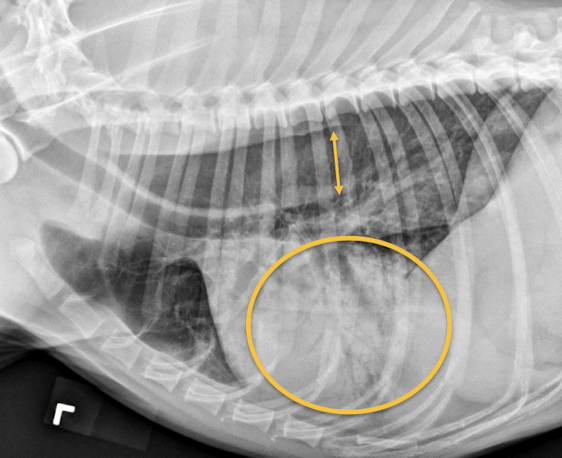

Juvenile idiopathic megaesophagus